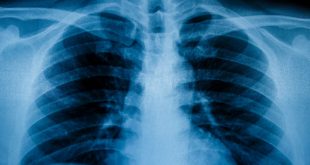

If you have ever broken a bone, or fallen ill with pneumonia, or experienced a painful toothache, you have …